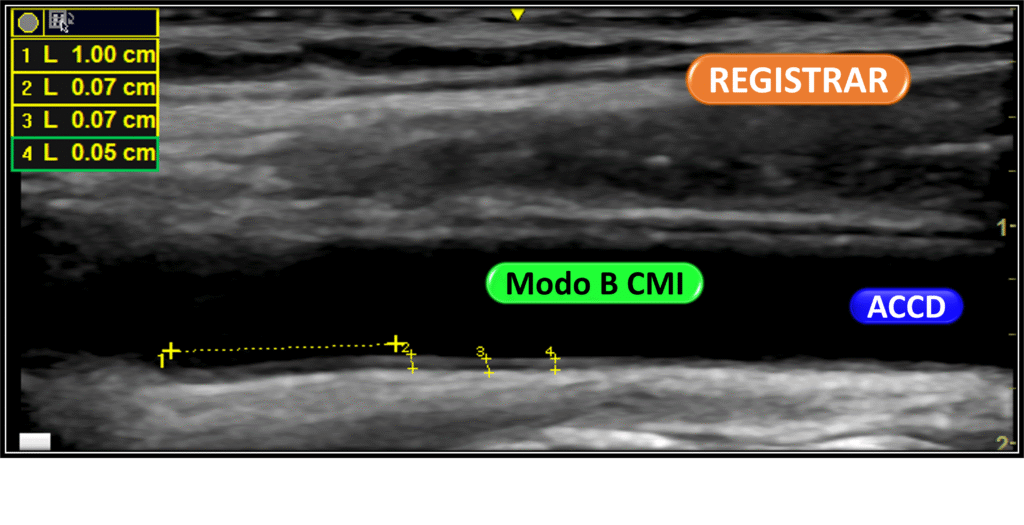

Imagens para registrar

O Doppler de carótidas é uma ferramenta fundamental para avaliar doenças arteriais.

Além da observação dinâmica em tempo real, é essencial registrar imagens que contenham as informações mínimas necessárias para um diagnóstico preciso.

Essas imagens devem incluir cortes longitudinais e transversais das artérias carótidas comuns, internas e externas. É importante destacar áreas de interesse, como placas, estenoses ou tortuosidades (kinks).

Também é indispensável registrar o Doppler colorido espectral com os valores das velocidades sistólicas e diastólicas — especialmente nas regiões com turbulência ou fluxo alterado.

Esses registros fotográficos permitem uma revisão diagnóstica mais segura e servem como base para comparações futuras, garantindo um acompanhamento detalhado e confiável da evolução das condições observadas.